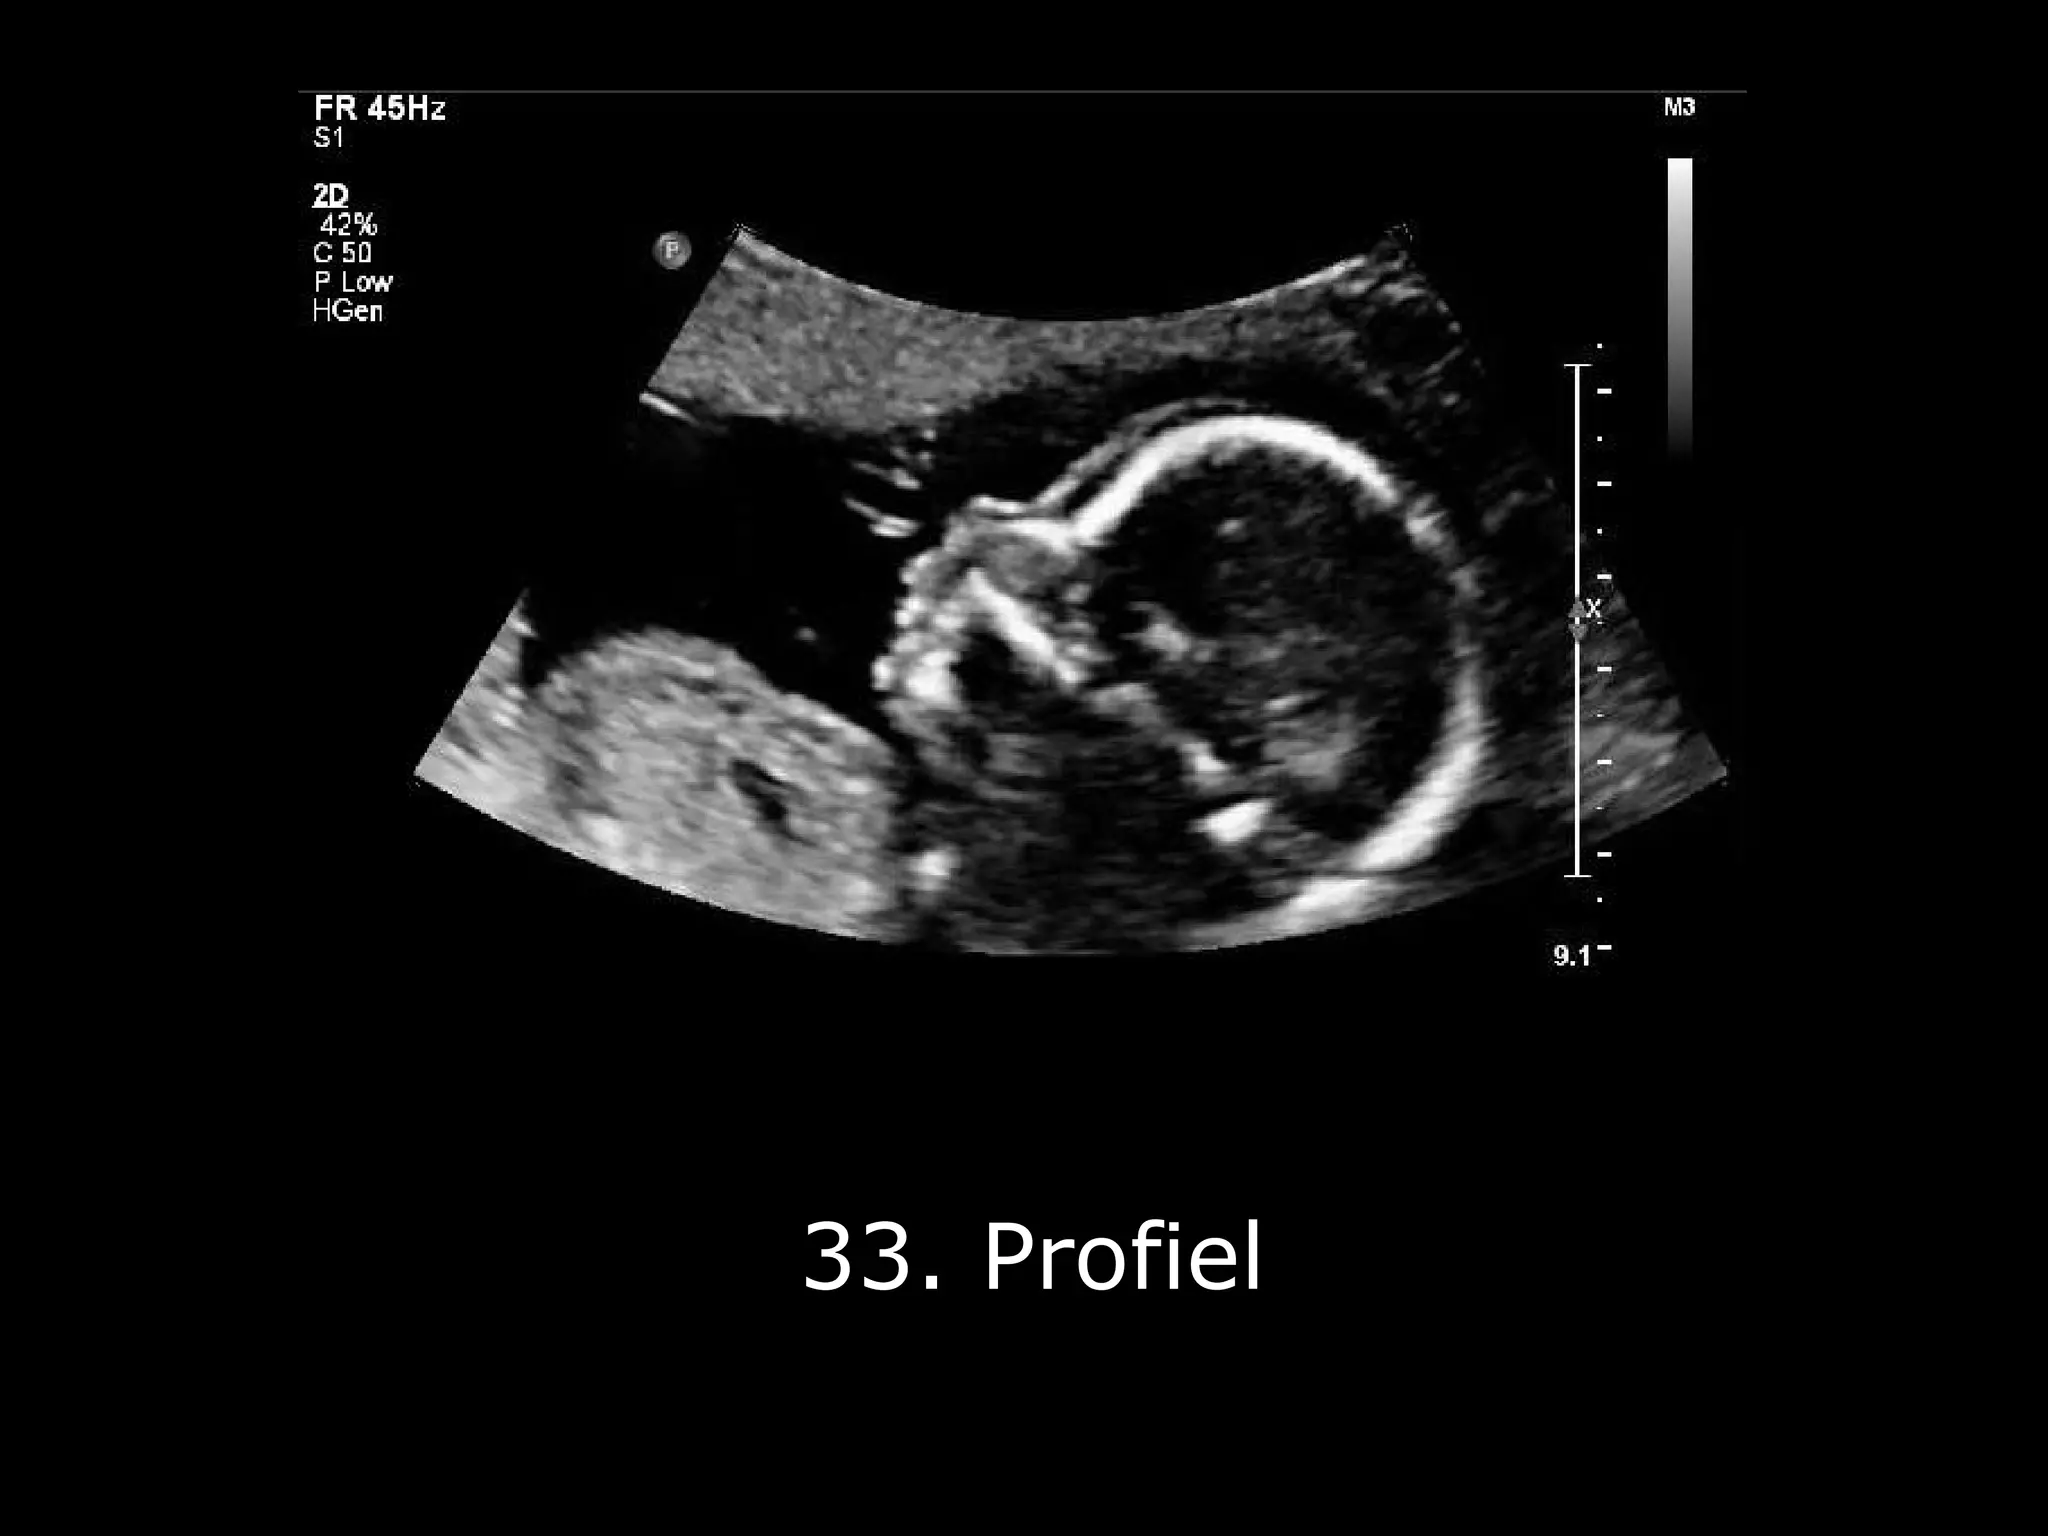

De 20-weken echo, ook wel de Structureel Echoscopisch Onderzoek (SEO) genoemd (moeilijk woord, hè?), is een uitgebreide check-up voor je baby. Zie het als een APK-keuring, maar dan voor een piepklein mensje in wording. Ze kijken echt alles na: de hersenen, het hartje, de niertjes, de ruggengraat... noem maar op!

Het is echt fascinerend om te zien. Alsof je een glimp opvangt van een geheim. En de echoscopist (wat een woord hè, net een goochelaar) is er om alles uit te leggen. Ze wijzen aan waar de beentjes zitten, of het hartje goed klopt (boem boem!), en of alles eruitziet zoals het hoort.